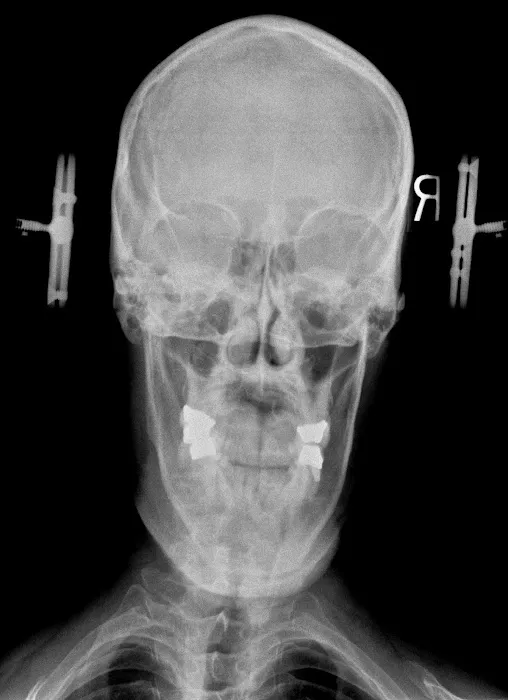

Chiropractic care is a healthcare profession focused on the diagnosis, treatment, and prevention of musculoskeletal disorders, with a primary emphasis on the spine and its impact on the nervous system. While traditional chiropractic often involves manual adjustments that may produce joint cavitation sounds (cracks), specialized approaches like Atlas Orthogonal chiropractic offer a distinctly different experience. This technique focuses on the Atlas vertebra (C1), the uppermost bone in the spine, and its relationship with the skull and the rest of the spinal column. Even a slight misalignment in this crucial area can impact the entire nervous system, leading to widespread issues. Dr. Thomas at Atlas Orthogonal Chiropractic, LLC, utilizes this highly precise, gentle method to realign the Atlas, often without any cracking. This precise adjustment aims to restore proper communication between the brain and body, alleviate pressure on nerves, and allow the body to heal naturally. This approach, combined with other therapeutic modalities, offers a powerful, non-invasive path to relief and long-term wellness.

Atlas Orthogonal Adjustments: This is the cornerstone and specialty of the practice. Utilizing a precise, gentle instrument, Dr. Thomas makes subtle adjustments to the Atlas vertebra (C1), without any twisting, popping, or cracking. This method aims to restore proper alignment of the head and neck, alleviating nerve pressure and allowing the body's natural healing processes to take over.